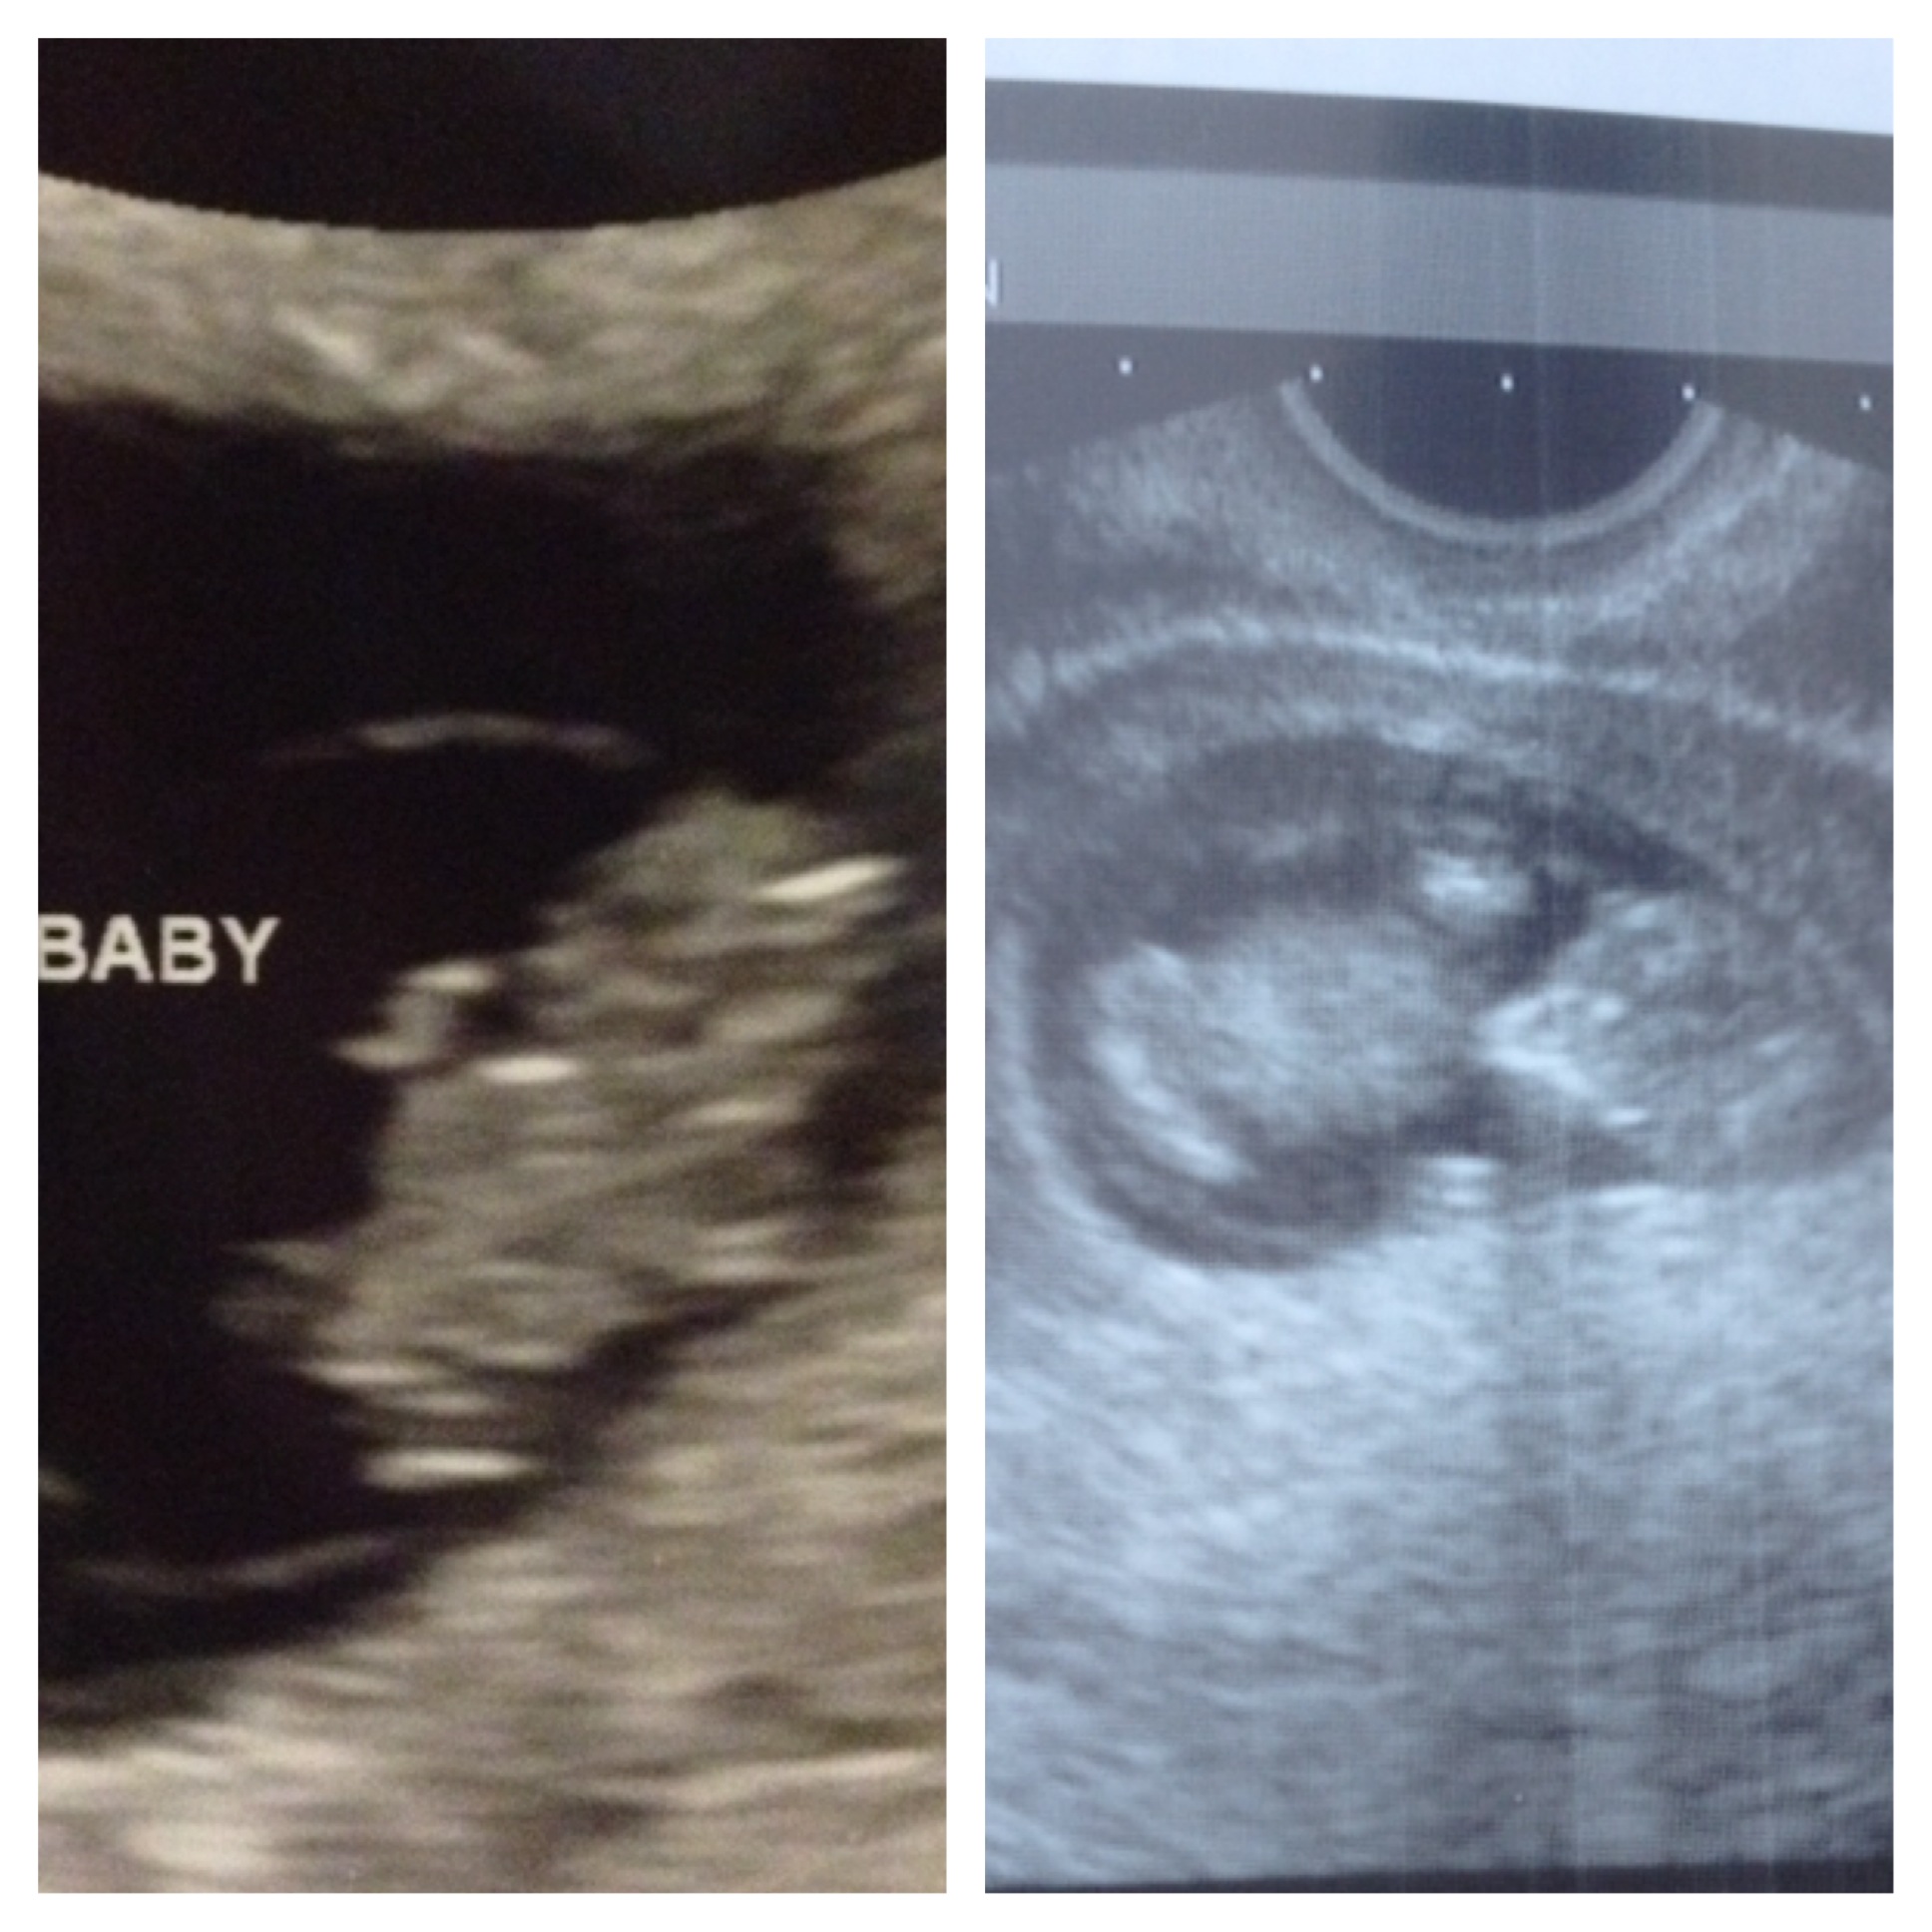

Today marks the 1 month point since I lost the baby. We would have been starting our 4th month of pregnancy today, and instead we are mourning and reflecting on 1 month since our loss.